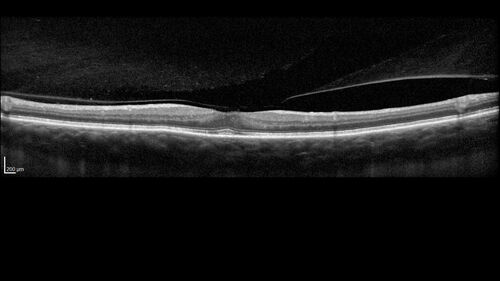

Choroidal Melanocystosis

65 year old female with normal vision.